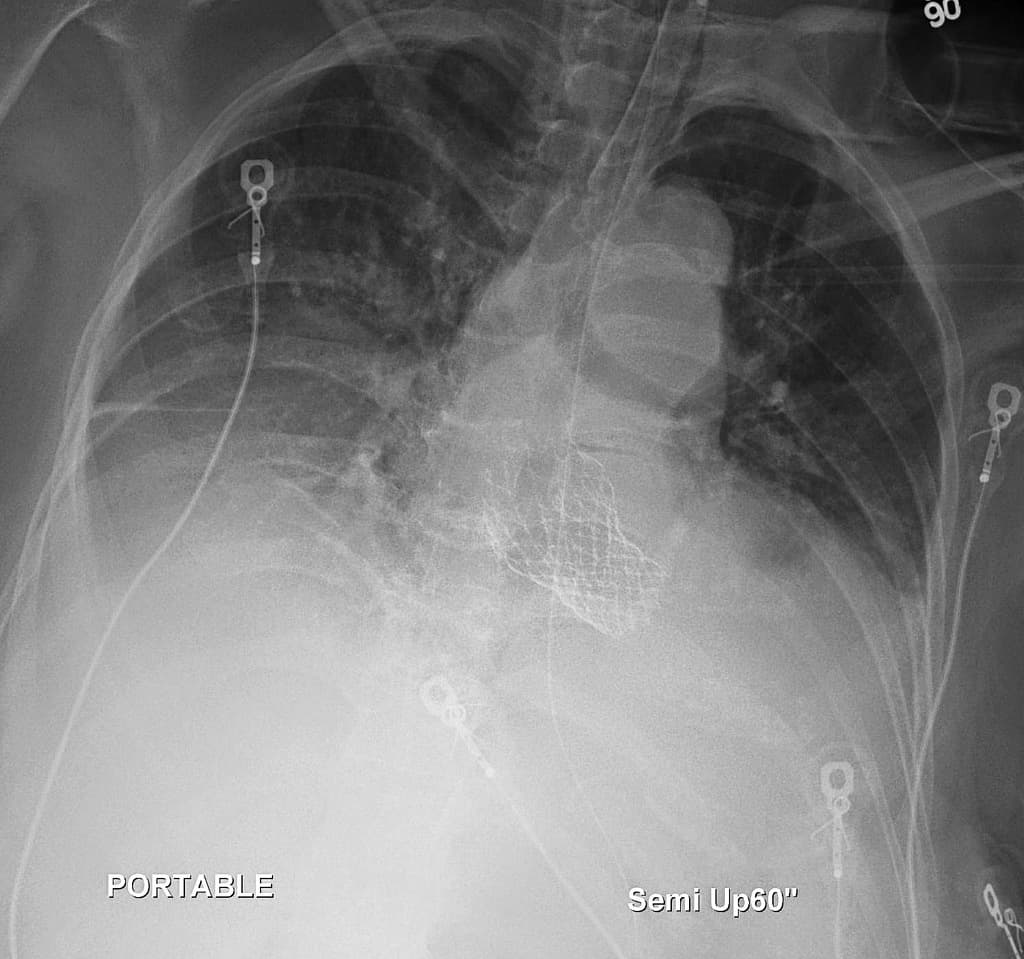

- Quan sát rõ nhất trên phim nghiêng là hình ảnh thay van động mạch chủ qua ống thông (transcatheter aortic valve replacement - TAVR), còn được gọi là cấy van động mạch chủ qua ống thông (transcatheter aortic valve implantation - TAVI).

- Máy tạo nhịp (pacing device) hai dây dẫn bên trái tại chỗ (in situ).

- Phổi có các thay đổi phù hợp với (consistent with) bệnh đường hô hấp tắc nghẽn mạn tính (COAD).

- Đám mờ giới hạn không rõ (ill-defined opacity) được ghi nhận ở cả hai vùng thấp, đại diện cho hình ảnh mô mềm phía trên chồng hình (superimposed) lên các xương sườn (ribs) và nhu mô phổi (pulmonary parenchyma).

Thay van động mạch chủ qua ống thông (transcatheter aortic valve replacement)

- "Khớp giả TAVR thường được nhìn thấy trong gốc động mạch chủ và thường được quan sát tốt nhất trên phim X-quang ngực nghiêng."

Thay van động mạch chủ qua ống thông (TAVR), còn được gọi là cấy van động mạch chủ qua ống thông (TAVI), là một phương pháp thay thế cho phẫu thuật thay van động mạch chủ (SAVR) cho những bệnh nhân bị hẹp van động mạch chủ nặng có triệu chứng, đặc biệt là những người có nguy cơ phẫu thuật cao. Thủ thuật này bao gồm việc triển khai một van sinh học thông qua ống thông, thường là qua đường động mạch đùi. Trên hình ảnh, van xuất hiện dưới dạng một khung giống stent cản quang nằm ở mức vòng van động mạch chủ. Các bác sĩ chẩn đoán hình ảnh nên biết về hình dạng điển hình này để tránh nhầm lẫn với các van phẫu thuật và để theo dõi các biến chứng như di lệch van hoặc việc đặt các thiết bị hỗ trợ tim liên quan.